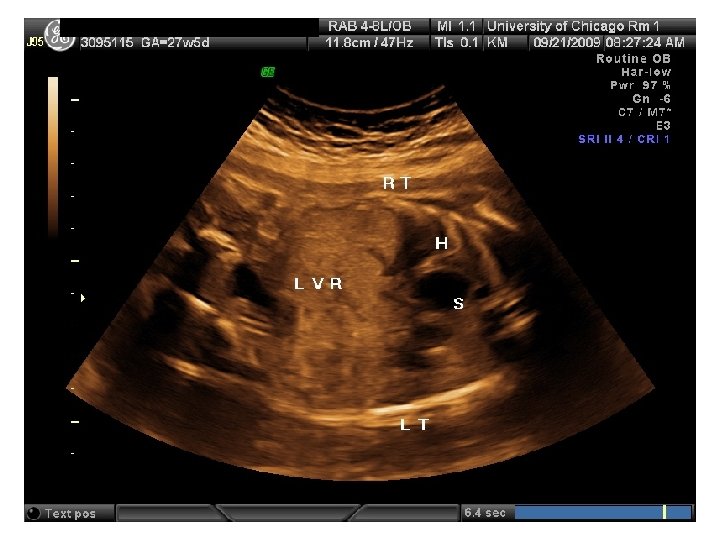

SR – Fetal Complete Heart Block 31 yo G 6 P 3114 EDC 10/20/09, now 33 wks, presented to HROB clinic at 10 wks for prenatal care. Fetal complete heart block was diagnosed at the routine 2 nd trimester anatomy scan. Pt is referred to The Fetal Center for multidisciplinary planning. PNC: 1. Systemic Lupus Erythematosus 2. Fetal Heart Block 3. H/O preeclampsia at 35 wks 4. Anemia – Presumed iron deficiency 5. Chronic HTN – No meds

SR – Fetal Complete Heart Block

SR – Fetal Complete Heart Block • Antenatal Plan – Weekly BPP with hydrops check • Delivery Plan – Primary Cesarean at 38 -39 wks with desired tubal ligation